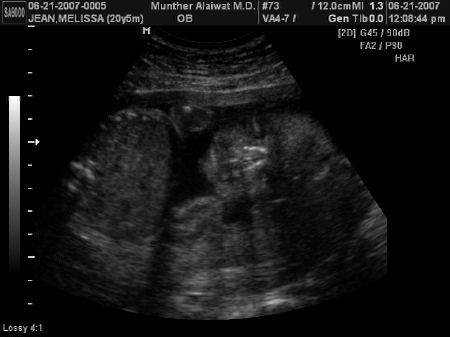

GIRL

Melissa Telling Cyril the News